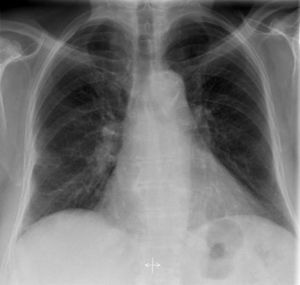

Chest xray..

Can anyone guess the diagnosis

TB

Cardiomegally?

Pulmonary embolism